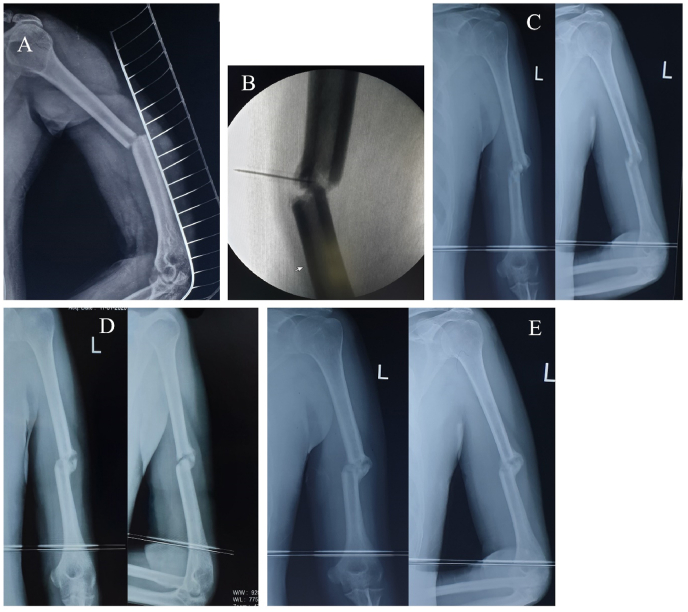

In every sitting, all the patients received 7–8 ml of autologous PRP at the site of delayed union of fracture with mean platelet counts of 2.13 × 106 platelets. Out of 25 cases, 21 (84.00%) cases showed good union of fracture with adequate callus formation by 10–12 weeks with 3 doses of autologous PRP injections. The mean time between surgical treatment and diagnosis of delayed bone union followed by PRP administration was 3.05 months. A total of 3 (12.00%) cases (2 cases of non-union and 1 case of implant failure) failed to unite by 3 doses of autologous PRP injection and hence converted to revision surgery along with bone grafting. One case with delayed union of midshaft right femur fracture was lost in our follow-up. No other complications were noted due to autologous PRP application among the study participants during the study period. The mean pre-procedural VAS score in our series was 6.12 ± 1.32 which was reduced to 1.31 ± 0.10 in the final follow-up in the 12th month. At the end of the 2nd and 3rd three weeks and 6th and 12th-month follow-up, the mean VAS score was statistically significant (p < 0.05) as mentioned in Table 2 and Fig. 1. The mean pre-procedural Warden's score was 0.93 which improved to 3.81 in the final follow-up in the 12th month. At the end of the 2nd and 3rd three weeks and 6th and 12th-month follow-up, the mean Warden's score was statistically significant (p < 0.05) as mentioned in Table 3 and Fig. 1. An illustrative case of management of distal femur delayed union with a retrograde nail and middle third humerus delayed union with autologous PRP injection and final follow-up have been depicted in Fig. 2, Fig. 3.

Fig. 2.

Illustrative case of management of distal femur delayed union with retrograde nail A: Pre-intervention status of delayed union at 4 months post fixation; B: Image-guidance autologous PRP injection; C: Follow-up at 3 weeks post PRP; D: Follow-up at 6 weeks post PRP; E: Follow-up at 9 weeks post PRP.